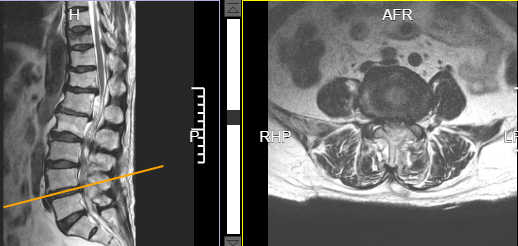

术前腰4/5椎间盘突出并椎管狭窄

术后腰4/5椎管减压后狭窄解除